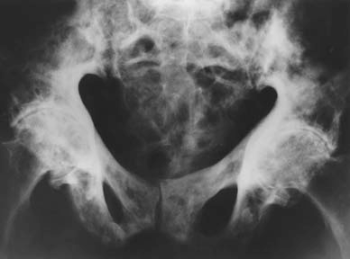

54.1.2. A csontok Paget-kórja